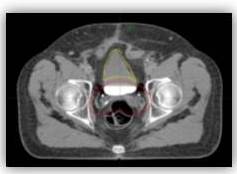

PRÓSTATA

En los casos de tratamientos prostáticos la RAVM es la modalidad primariamente usada. El paciente es colocado de cubito supino y se usan Rayos X de 6 MV. Se emplean arcos axiales con amplitudes de 165° y 195°. El tratamiento dura alrededor de 3 min a diferencia de RTIM el cual toma alrededor de 8 min. A continuación se muestra el plan de tratamiento en planos axial, coronal y sagital para el tratamiento de una lesión prostática.